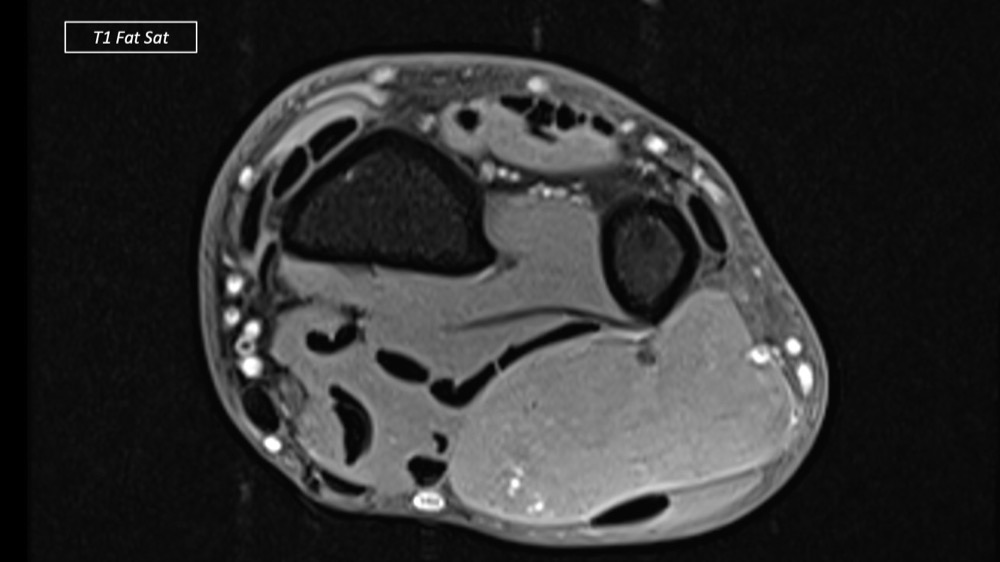

Dupuis / Benoist / Leclerc / Bousson 18/05/2022